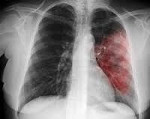

7. Рентгенография грудной клетки: зависят от стадии течения заболевания:

В первый день рентгенологически можно нередко выявить лишь усиление легочного рисунка, затем появляются участки затемнения, постепенно целиком охватывающие сегмент или долю легкого, что соответствует стадии инфильтративных изменений.

Через 2—3 недели гомогенное затемнение легочной ткани, занимающее сегмент, долю или несколько долей, локализуется чаще в нижней и средней долях правого легкого; имеет четкий контур тени.